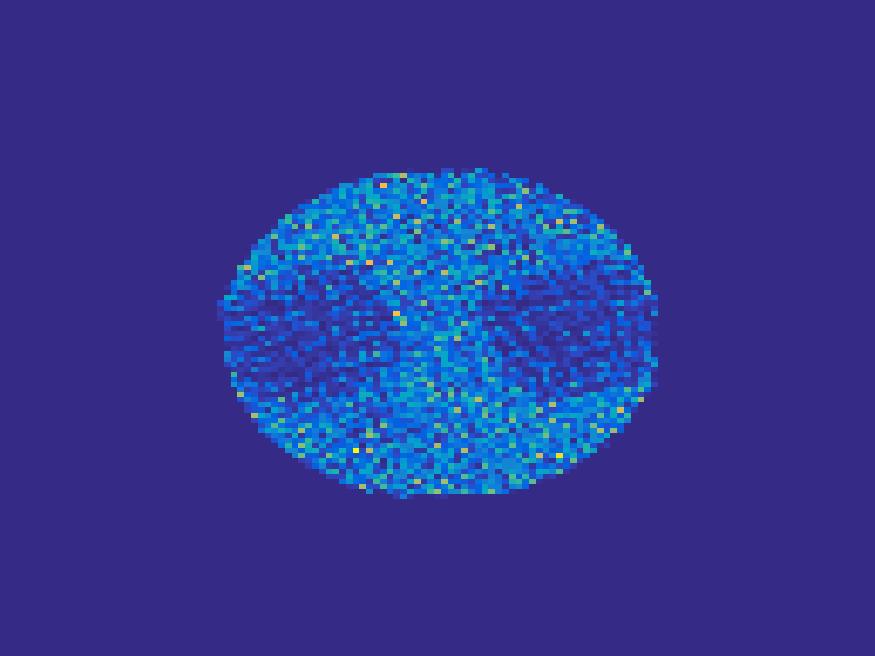

The proposed method is tested on numerical phantoms for a proof of concept study. We simulate image frames of size and projections per frame. Three time activity curves (TAC) for blood, liver and myocardium, previously used in [14] (see Figure 1), are used to simulate the dynamic images. The first simulated dynamic phantom is composed of two ellipses. In temporal direction, the positions of the two ellipses are stationary while the intensity in 90 frames within the region of each ellipse is generated according to the TAC of blood or liver. The projections are generated by using Radon transform sequentially performed for each frame.

In the tests, projections at two orthogonal angles are simulated for every frame to mimic 2-head camera data collection. The projection angles increase sequentially by along temporal direction. For example, at frame 1, projections are simulated at angle and , and at frame 2, angle and , etc. Finally, white Gaussian noise is added to the projection data. Reconstruction results with different methods are shown in Figure 3. Since the number of projections is very limited for each frame, the traditional FBP and least square methods cannot reconstruct the images satisfactorily, while the proposed method is capable to reconstruct the images effectively. Compared with SEMF model, when the edge of images jump (see frame 21 -frame 31 in Figure 3), the proposed model can better capture the change of the tendency of TAC.

| Frame 1 | Frame 11 | Frame 21 | Frame 31 | Frame 41 | Frame 51 | Frame 61 | Frame 71 | Frame 81 |